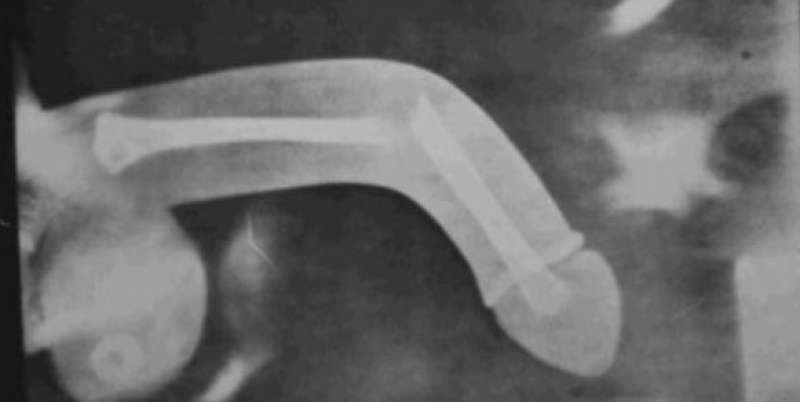

La frattura può avvenire in qualsiasi punto del pene, ma generalmente si verifica alla base e coinvolge la tonaca albuginea ed un solo corpo cavernoso. Una frattura del pene farà sì che il pene assuma quella che i medici chiamano deformità da melanzana, dove il pene appare viola e gonfio. Caro utente,calma e.gesso.la frattura del pene, per la sua drammaticità sintomatologica,non lascia spazio a. La frattura del pene o sindrome del chiodo rotto è una lesione dell'organo sessuale maschile, che può verificarsi in quali sono i rimedi per la frattura del pene? Sezione longitudinale che mostra la rottura della tunica albuginea con un. Essa avvolge i due organi che irrorati di sangue consentono all'uomo di avere. La frattura del pene o peniena, anche denominata sindrome del chiodo rotto, è un raro trauma del pene che consiste nell'improvvisa e dolorosa rottura della tonaca albuginea dei corpi cavernosi, dovuta a un colpo violento verificatosi durante l'erezione. L'età critica è quella compresa tra i 30 e i 40 anni e in. Il trattamento della frattura del pene può essere di tipo conservativo o chirurgico. Una frattura del pene è uno strappo nella tunica albuginea. L'età più comune in cui può verificarsi una rottura del pene evento va dai 18 ai 66 anni. La frattura del pene è una condizione clinica relativamente rara. See more of fractura de pene on facebook. Sintomi più rari di una frattura del pene sono. Frattura di questo corpo può avere. Il trattamento chirurgico è attualmente considerato il metodo migliore, avendo dimostrato di portare a risultati migliori. Il fenomeno e' causato da una improvvisa, forzata e innaturale.